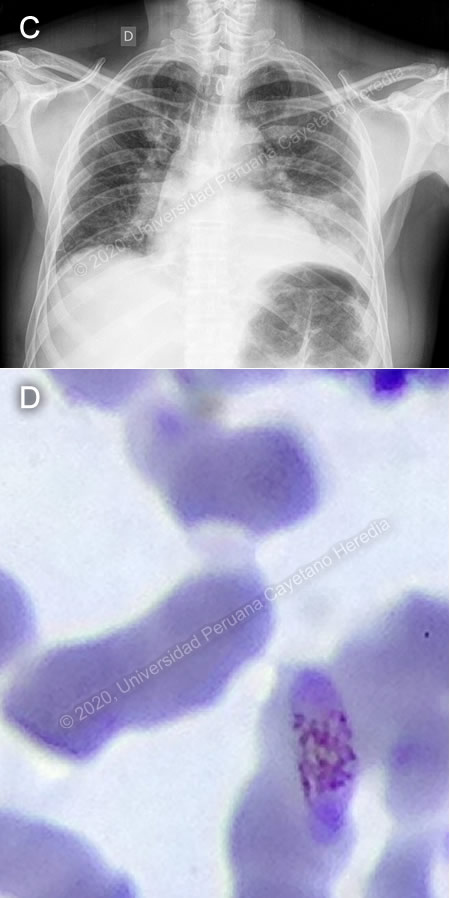

![]() Discussion: P. vivax schizonts and gametocytes (Images A, B) were found on initial thick smear. There was concern for severe malaria due to the patient’s presentation, with hypotension, elevation of bilirubin, and altered renal function. One day later, the patient reported shortness of breath, with oxygen saturation to 77%, requiring supplemental oxygen. Chest X-ray showed a new consolidation in right base (Image C). Then, new slides prepared from the same blood samples collected on admission revealed P. falciparum gametocytes (Image D). "An “Effective” (Hangzhou AllTest Biotech) rapid antigen detection test was positive for P. vivax but negative for P. falciparum. This test contains P. vivax anti-HRP-II and anti-pLDH antibodies and P. falciparum anti-HRP-II antibodies. This rapid test has a reported sensitivity of 95% and specificity of 99% for P. vivax and P. falciparum, when compared to microscopy [Cochrane Database of Systematic Reviews 2014, doi: 10.1002/14651858.CD011431] Discrepancy between the microscopy findings and rapid test results for our patient may be explained by absence of HRP proteins due to pfhrp2 or pfhrp3 deletions in some P. falciparum parasites. Peru has the highest documented levels of such deletions [PloS One 2010, doi: 10.1371/journal.pone.0008091]. Genetic analysis conducted on 188 P. falciparum samples collected in Peru showed that pfhrp2-negative parasites have multiple origins, and possibly evolved independently [Sci Rep. 2013, doi: 10.1038/srep02797]. Prevalence of this character is highly variable in other parts of the world [WHO, Global Malaria Program 2016]. The differential diagnoses of an acute febrile illness in a patient coming from the north coast of Peru include malaria, dengue, typhoid fever, brucellosis and leptospirosis. When considering dengue, the absence of a rash and the duration of the fever made the diagnosis less likely. Typhoid fever and brucellosis are farther down in the list of differential diagnoses due to the patient’s clinical course. Typhoid does not typically present with thrombocytopenia, whereas brucellosis typically presents with arthralgia. Leptospirosis is usually accompanied by marked jaundice and renal failure. In Peru, there has been an average of 2,530 cases of malaria reported annually from 2015 to 2019, most of them in the Amazon region [CDC Peru]. Management approach relies on the species identified, resistance to antimalarial drugs, and severity of disease. Oral treatment with artemisinin-based combination therapy (ACT) for 3 days is the recommended first-line treatment against both P. vivax and P. falciparum. In P. vivax infection, a 14-day course of primaquine should be added to prevent recurrence. In Peru, due to a low prevalence of G6PD deficiency, patients are not typically tested prior to treatment with primaquine. If there is concern for severe malaria, intramuscular or intravenous artesunate should be used for at least 24 hours and until patients can tolerate oral therapy, then complete treatment with 3 days of ACT. [WHO 2015] WHO defines severe malaria as the presence of one or more of the following clinical indicators: deep coma suggestive of cerebral malaria, prostration or generalized weakness with inability to walk, two or more seizures within 24 hours, pulmonary edema, ARDS, shock, significant bleeding. It may also be accompanied by laboratory indicators such as severe malarial anemia (Hct: <20%, Hb: <7g/dL), renal failure (serum creatinine >3mg/dL), hypoglycemia (<40mg/dL), hyperparasitemia (>10%), acidosis and hyperbilirubinemia (serum bilirubin >3.0mg/dL). Progression to severe and fatal disease is largely but not entirely confined to P. falciparum. In the case presented, the patient was judged to be at high risk for progression to severe malaria due to hypotension at presentation and altered renal function tests, serum bilirubin, and lactate. Strictly speaking, he did not fulfill WHO criteria for severe malaria; however, he did not tolerate oral medications at the time of admission, and so was started on IV artesunate, of which he received a total of 3 doses. Afterwards, he received a full 3-day course of oral artesunate-mefloquine, followed by 7 days of oral primaquine. In Peru, most cases are caused by P. vivax or P. falciparum, with occasional reports of P. malariae. Official Peruvian data report mixed infection in 17 of 54,627 reported malaria cases for 2016 [CDC Peru]. However, studies from malaria endemic regions in Southeast Asia report nested-PCR-detected rates of mixed infection as high as 23.5%, where microscopy methods only detect 0-2.5% [Indian J Med Res 2010; 132:31-5]. Underreporting of mixed malaria infection is frequent, due to limitations in diagnostic methods. It is important to accurately diagnose mixed malaria infections because treatment may need to be altered in order to ensure clearance of parasitemia [Malar J 2011, doi: 10.1186/1475-2875-10-253]. One of the most important, although rare, complications of severe malaria is secondary bacterial infections. Increased risk of bacteremia in children with severe malaria has been previously described [Lancet 2011, doi: 10.1016/S0140-6736(11)60888-X]. Bacteria isolated in malaria patients (usually P. falciparum) include Salmonella (typhi, typhimurium, paratyphi), Staphylococcus aureus, and Escherichia coli [Am J Trop Med Hyg 2018, doi: 10.4269/ajtmh.18-0378, Open Forum Infect Dis 2016, doi: 10.1093/ofid/ofw028]. Our patient was started on IV ceftriaxone and clarithromycin because of the new consolidation on the chest X-ray, with marked clinical improvement over the next days. |